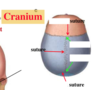

What are the two layers of the dura mater? What do the partitionings form?